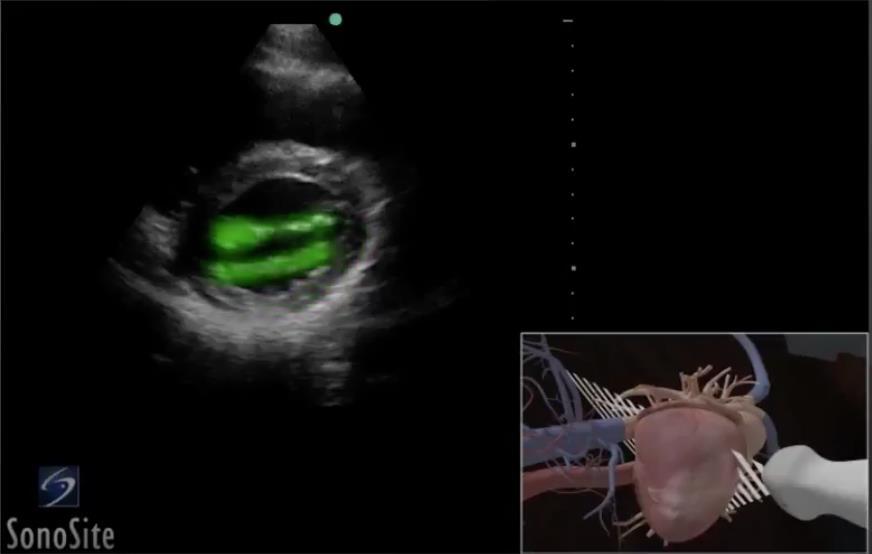

Heart Parasternal Short Axis (PSAX) Highlighted Mitral Valve Image

Highlighted Area: Mitral Valve